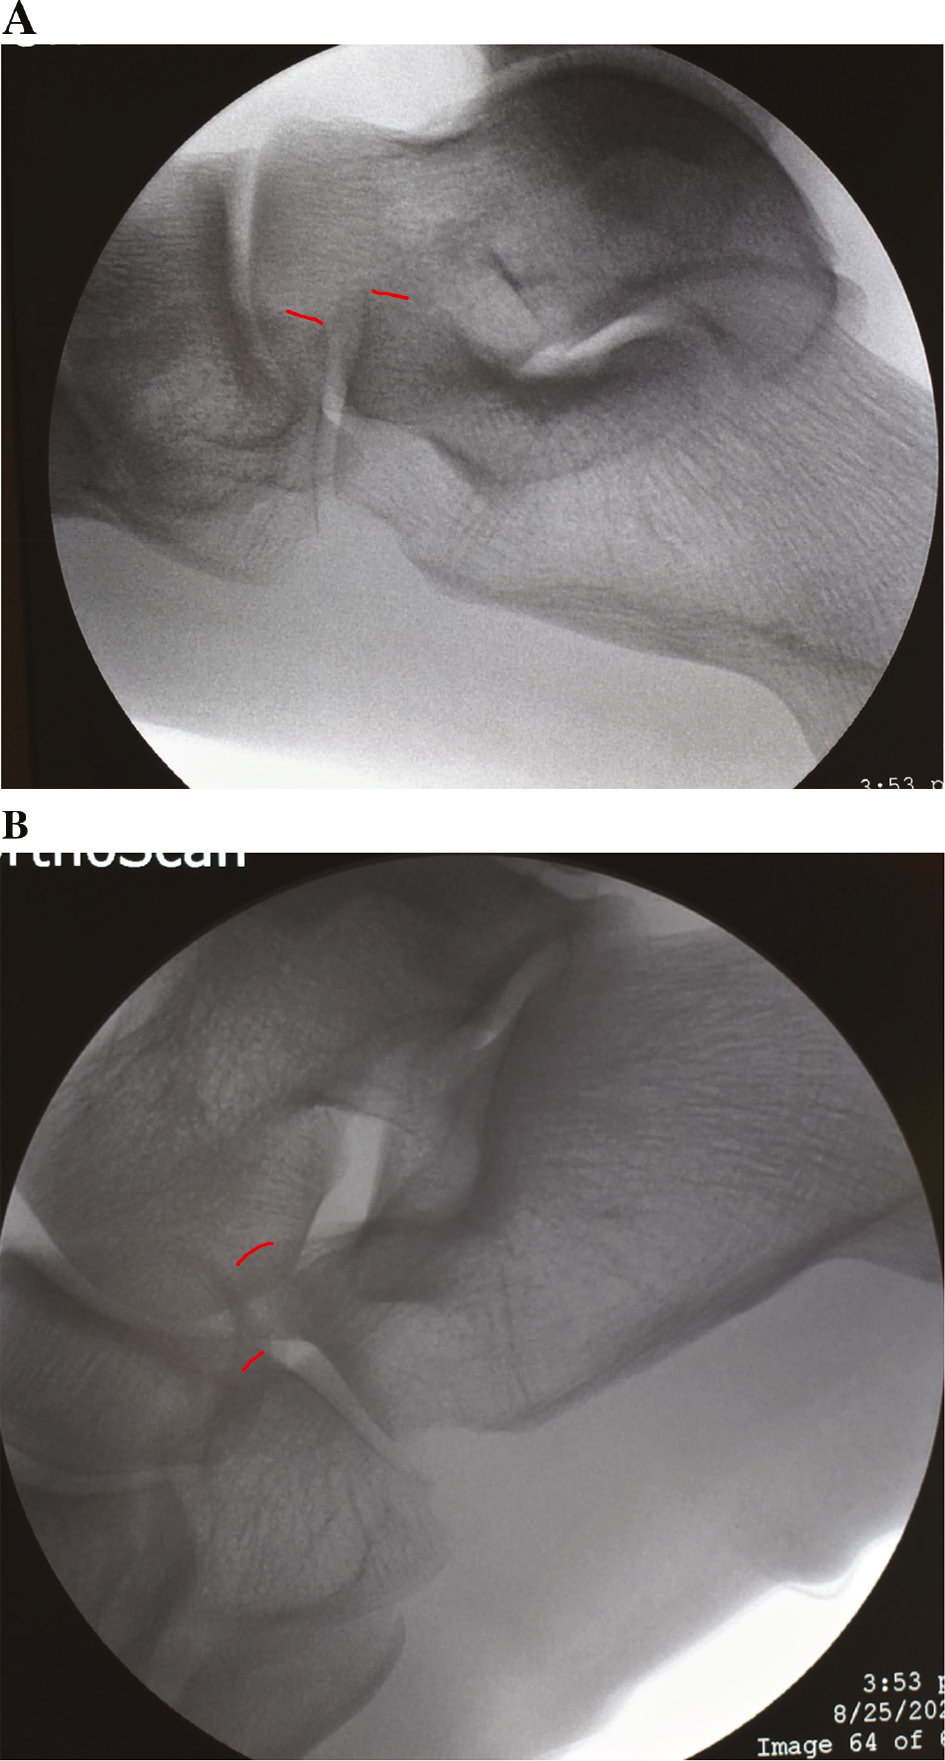

The patient is a 14-year-old male weighing 114.4 kg (>99th percentile) with a history of bilateral symptomatic pes planovalgus unresponsive to multiple modes of conservative treatment over 2 years. Physical examination demonstrates standing right hindfoot valgus and planus. The heel inverts with toe raise. In a subtalar neutral position, ankle dorsiflexion is 15 degrees short of neutral with the knee extended. Radiographs demonstrate planovalgus of the right foot (Figure 1).

Figure 1. (A) AP, (B) oblique, and (C) lateral preoperative radiographs demonstrating pes planovalgus and initial joint alignment of CC joint.